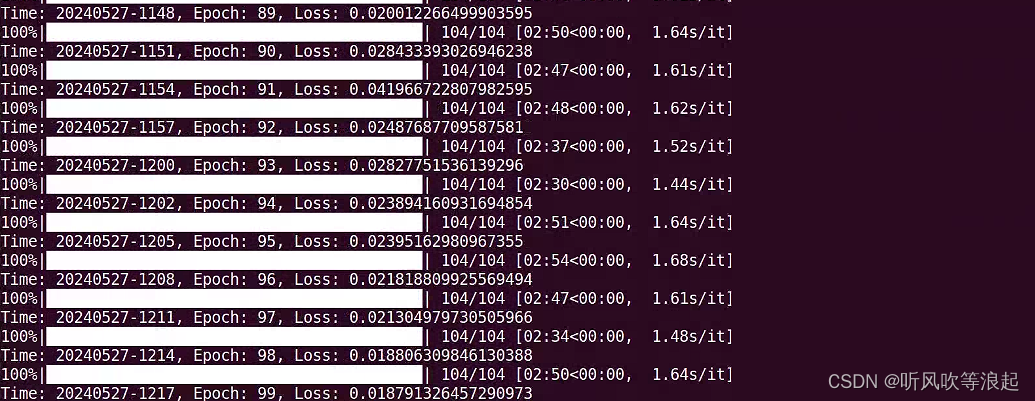

效果如下:

这里epoch改成了100